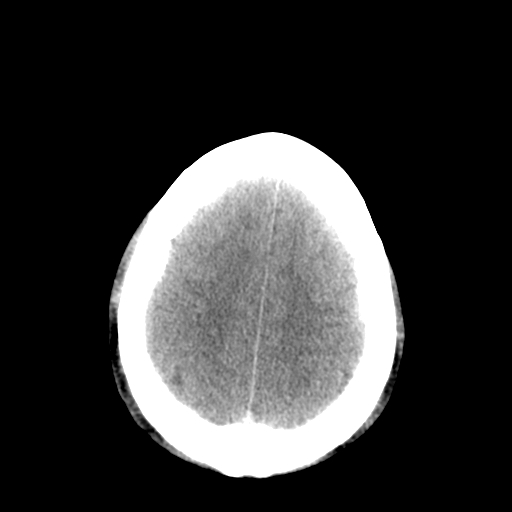

以下是引用李衡钧在2008-9-18 17:37:00的发言:[br]脑质内见两个低密度灶,其内见点状高密度。[br]考虑脑囊虫。建议增强或进一步检查确诊。

以下是引用chmh在2008-9-18 18:45:00的发言:[br]考虑脑囊虫病可能性大,建议行ct增强检查及血清和脑脊液囊虫补体结合试验.